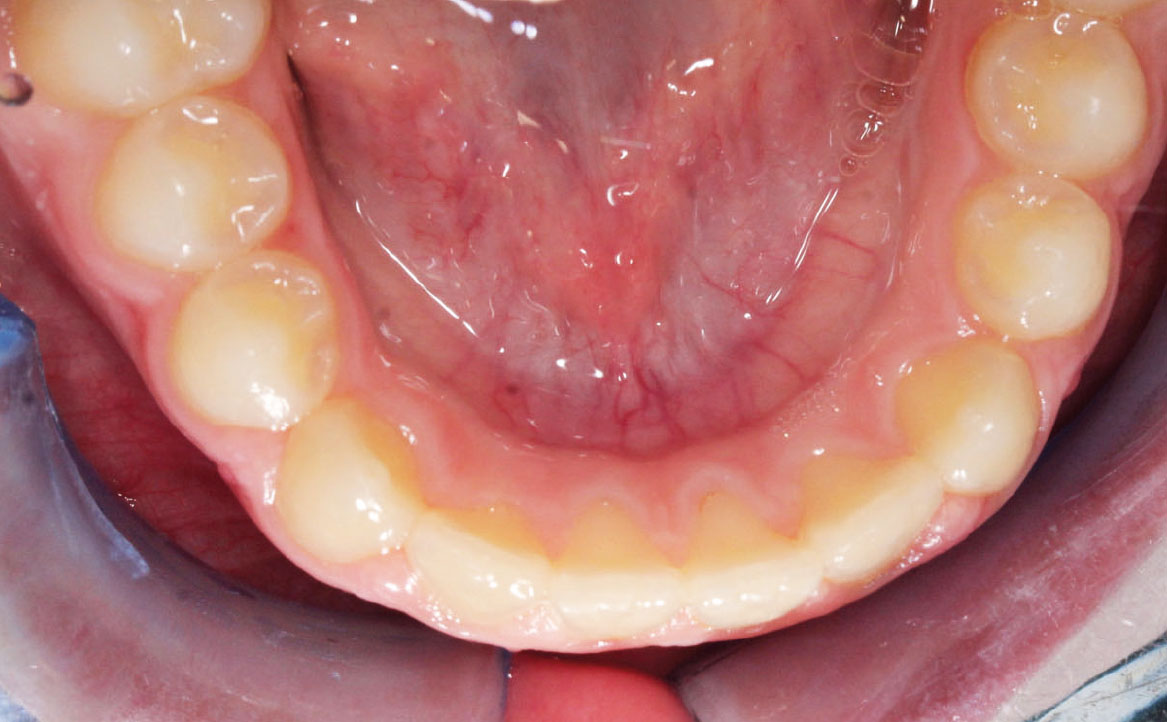

Fig. 7B Modello digitale dell'arcata inferiore.

L’overjet e l’overbite sono entrambi ridotti in massima intercuspidazione. Trasversalmente il mascellare superiore è contratto (fig. 4-7).

All’esame obiettivo si osserva prima classe molare bilaterale e classe canina non valutabile poiché il paziente si trova in fase di dentizione mista con permuta in atto degli elementi dentari decidui. L’analisi cefalometrica evidenzia Ia classe scheletrica tendente alla III, ipodivergente. Dal primo contatto alla massima intercuspidazione si rileva la presenza di uno shift mandibolare che determina uno scivolamento mandibolare anteriore: ne risulta overjet negativo e overbite ridotto. La postura linguale del paziente è anteriore e la deglutizione atipica. Sul piano trasversale è osservabile una contrazione del mascellare.